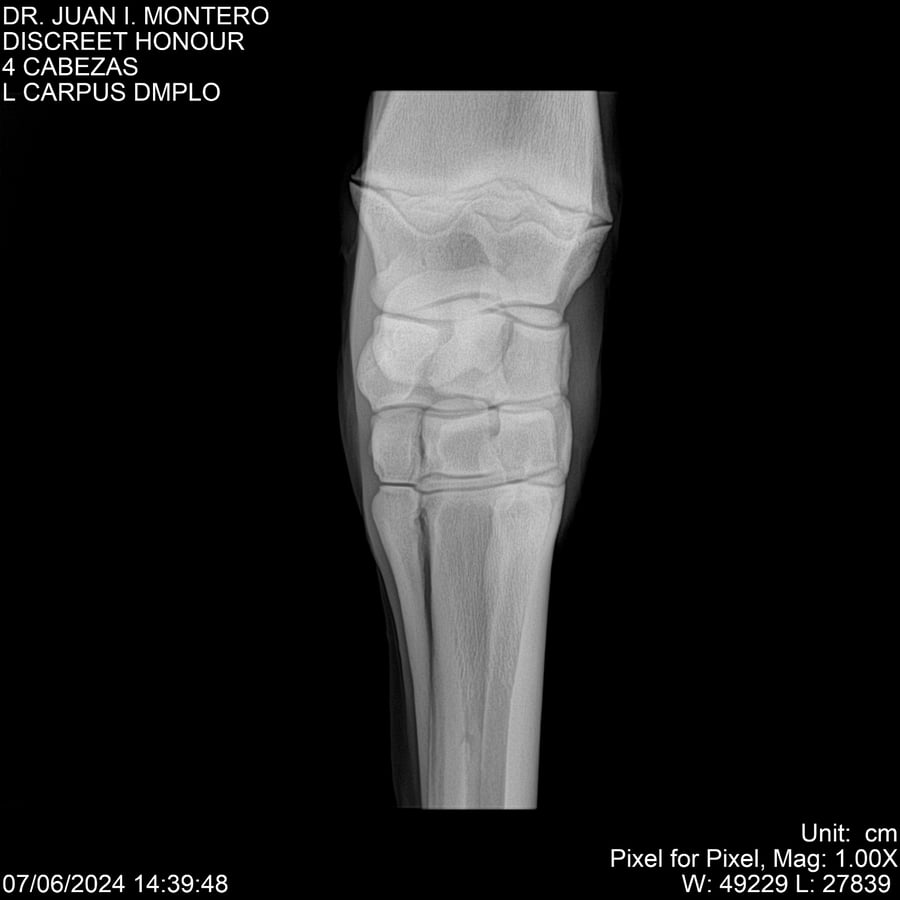

LOTE 6, DISCREET HONOUR 🔥 🔥 🔥 Lote Anterior Volver al remate Lote Siguiente Ficha Contacto Montevideo - Ficha del Lote Identificador: #281093 Categoría: Yeguarizos Montevideo - 82 Visualizaciones ClicData Contacto Empresa: Abelenda N. R., Walter Hugo Nombre*: Teléfono* : E-mail* : Mensaje Enviar Registrese gratis Este contenido Exclusivo está disponible sólo para usuarios registrados Ingresar